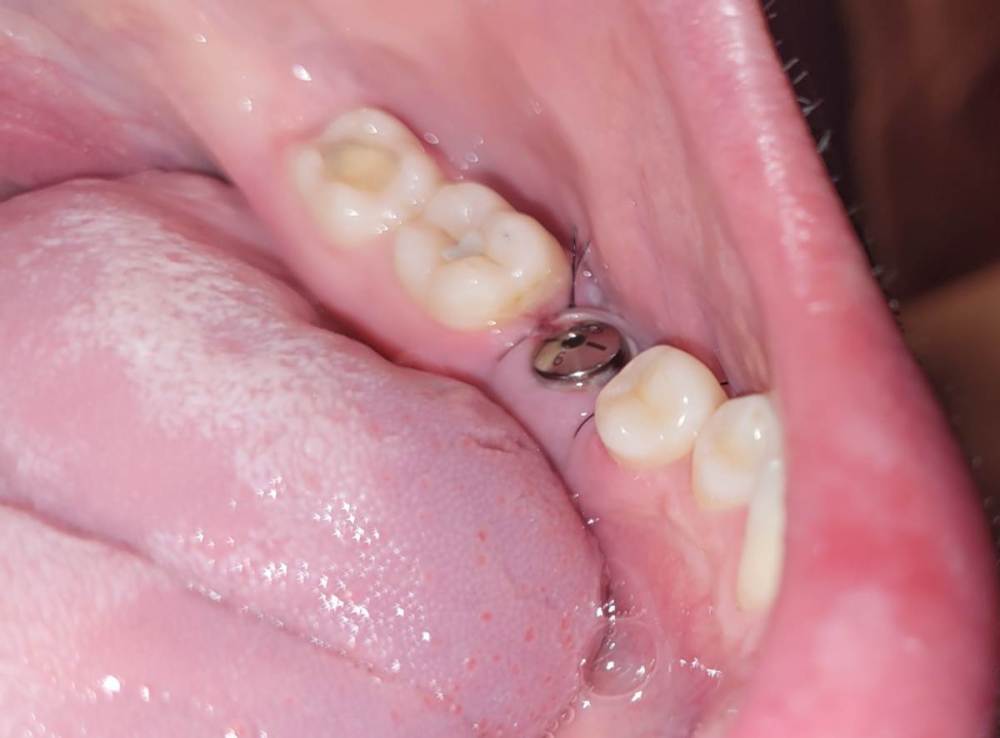

Dimarik12 Опубликовано 12 мая, 2022 Автор Поделиться Опубликовано 12 мая, 2022 @red_butler прикрепляю фото. Кажется, из-за наклона имплантата, фдм расположена сильно близко к семёрке, а с пятеркой будет щель. У меня опасения о неравномерном нагружении протеза и его преждевременной повреждении. Ps.ошибся вчера, отсутствует правая пятёрка. Ссылка на комментарий